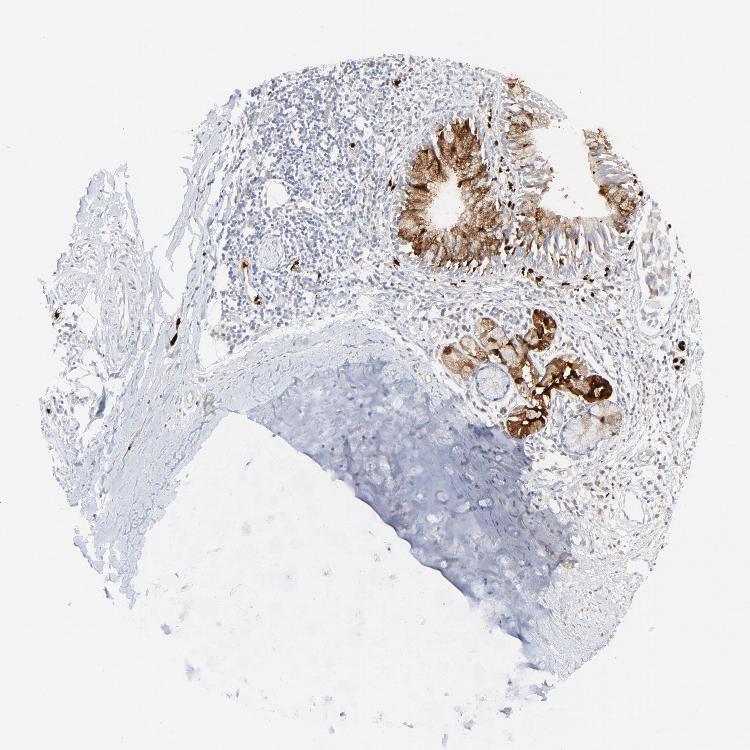

SOFT TISSUE 1 - Antibody stainingi

Antibody staining in the annotated cell types in the current human tissue is reported as not detected, low, medium, or high, based on conventional immunohistochemistry profiling in selected tissues. This score is based on the combination of the staining intensity and fraction of stained cells.

Each image is clickable and will lead to virtual microscopy that enables deeper exploration of all samples and also displays staining intensity scores, fraction scores and subcellular localization as well as patient and tissue information for each sample.

Antibody HPA002695Antibody CAB016549Antibody CAB016550

Chondrocytes Not detected--

Fibroblasts Not detectedNot detectedNot detected

Peripheral nerve Not detectedNot detectedNot detected